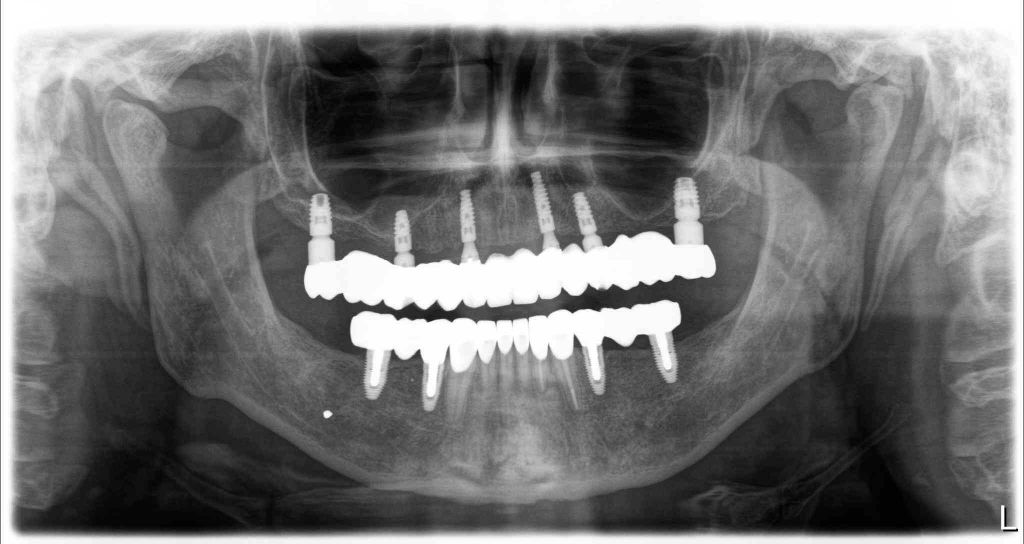

There is no question that dental implants have revolutionized tooth replacement and the practice of dentistry. Today’s highly successful dental implants consist of an artificial tooth root, to which a crown is attached. This system looks just like the natural teeth in your mouth when you smile: there is no visible difference. In addition, Implants do not decay and are relatively free from developing gum disease.

The practice of implant dentistry requires expertise in planning, surgical placement and crown fabrication: it is as much about art and experience as it is about science. It also requires teamwork between you and your dentist, and implant surgeon, and a dental technician.

Zirconia bridge on Southern DC Implants

Tooth Replacement

Zirconia Implants